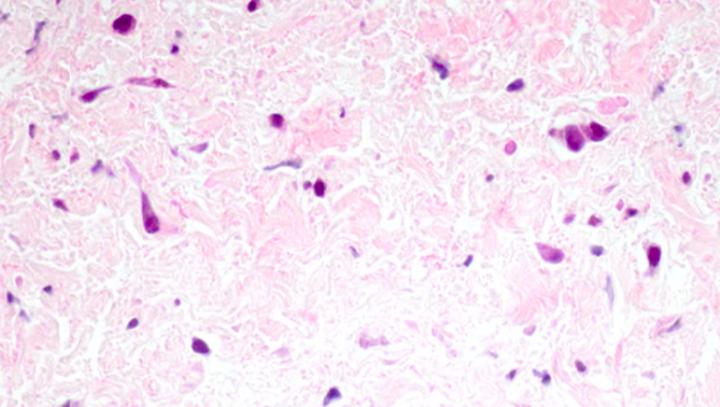

Pulmonary vein stenosis (PVS) is a rare disease in which abnormal cells build up inside the veins responsible for carrying oxygen-rich blood from the lungs to the heart. It restricts blood flow through these vessels, eventually sealing them off entirely if left untreated. Typically affecting young children, the most severe form of PVS progresses very quickly and can cause death within a matter of months after diagnosis.